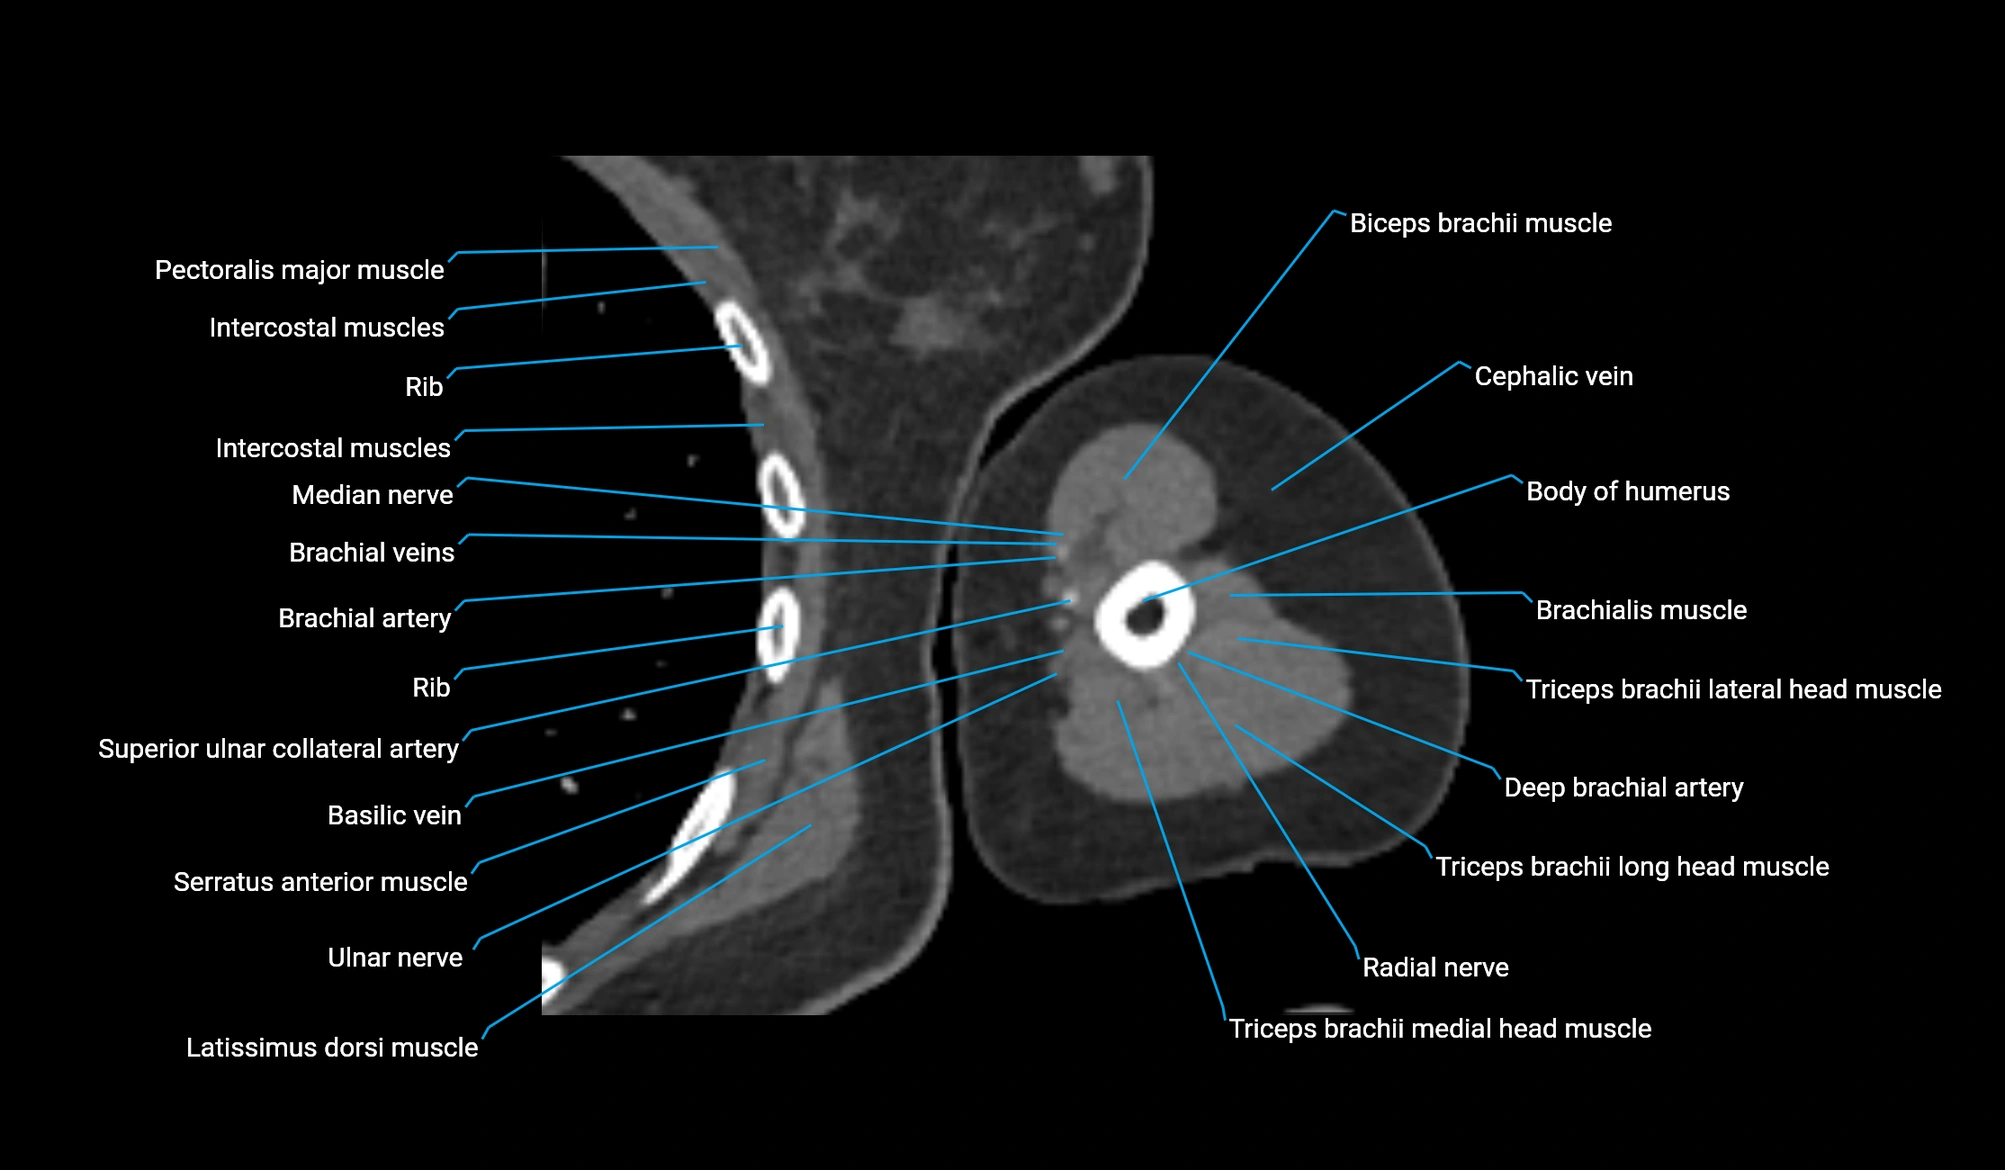

- Body of humerus

- Brachial artery

- Brachialis muscle

- Cephalic vein

- Deep brachial artery

- Median nerve

- Radial nerve

- Superior ulnar collateral artery

- Ulnar nerve